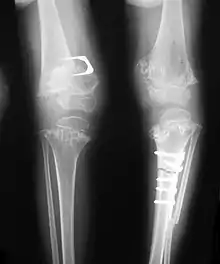

Skeletal radiography

Accurate assessment of plain radiographic findings remains an important contributor to diagnosis of pseudoachondroplasia. It is noteworthy that vertebral radiographic abnormalities tend to resolve over time. Epiphyseal abnormalities tend to run a progressive course. Patients usually suffer early-onset arthritis of hips and knees. Many unique skeletal radiographic abnormalities of patients with pseudoachondroplasia have been reported in the literature.[2][7][4]

- Together with rhizomelic limb shortening, the presence of epiphyseal-metaphyseal changes of the long bones is a distinctive radiologic feature of pseudoachondroplasia.

- Dysplastic/hypoplastic epiphyses especially of shoulders and around the knees.

- Metaphyseal broadening, irregularity and metaphyseal line of ossification. These abnormalities that are typically encountered in proximal humerus and around the knees are collectively known as “rachitic-like changes”.

- Radiographic lesions of the appendicular skeleton are typically bilateral and symmetric.